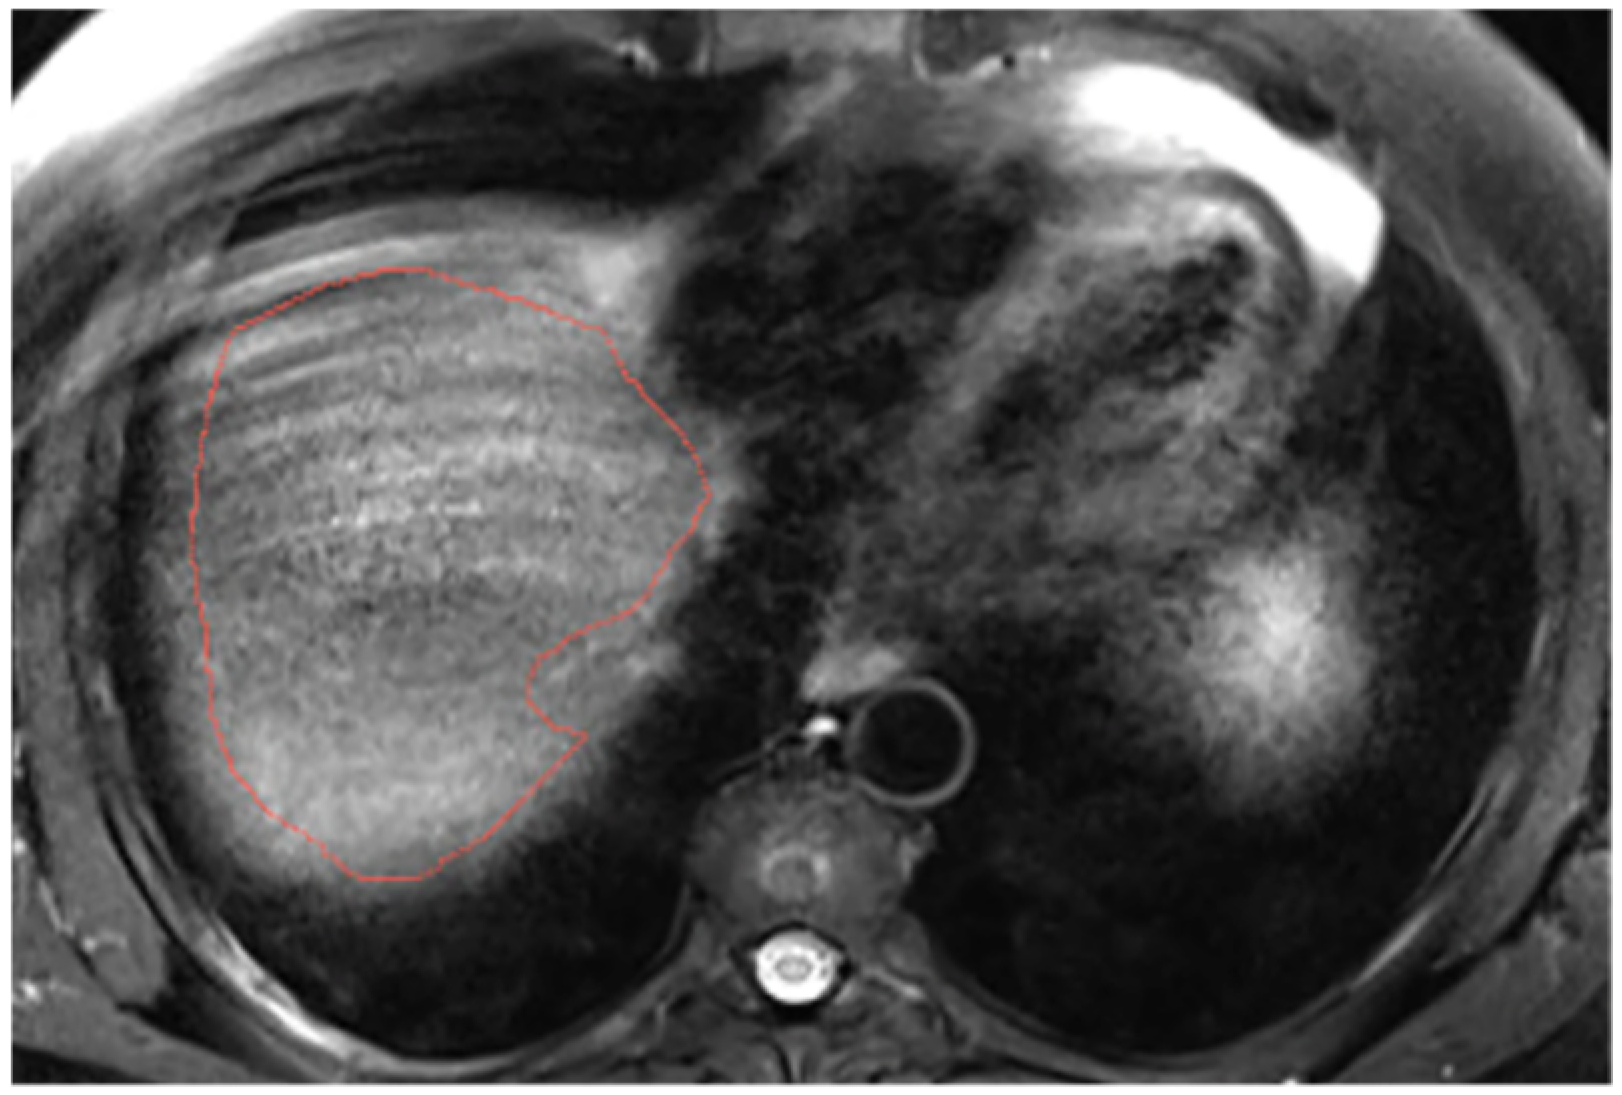

Appendix A.6. Presence of Respiratory Artifacts